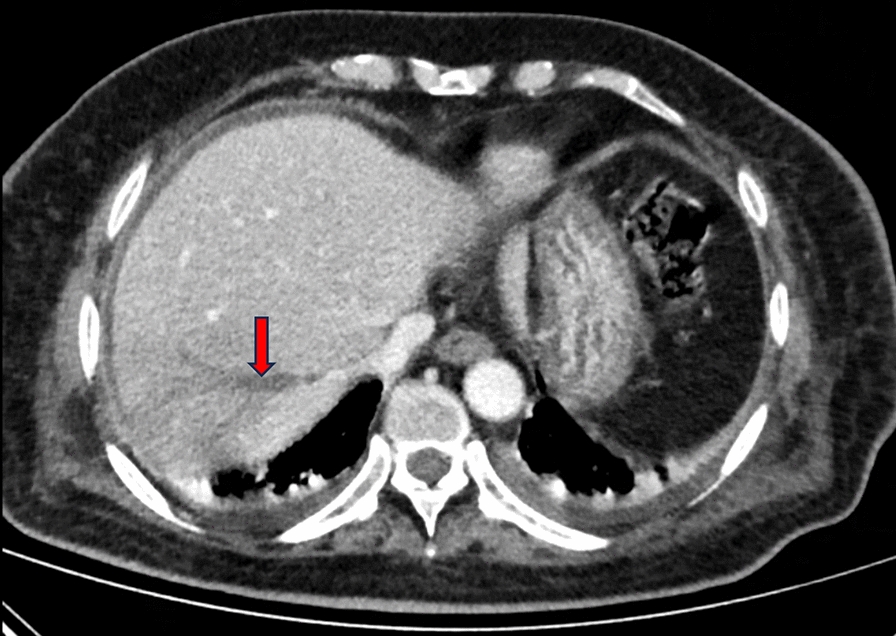

Case report: A 75-year-old Han Chinese female patient who presented to the emergency department primarily for fever accompanied by chills was diagnosed with pyogenic liver abscess complicated with pulmonary infection, involving multiple pus emboli in the branches of the right hepatic vein. The patient accepted intravenous imipenem and cilastatin sodium for anti-infection, and subcutaneous insulin to control hyperglycemia. Percutaneous liver puncture and drainage was performed under ultrasound guidance. During the treatment the patient presented with headache, weakness in both lower limbs and lower back pain. Brain magnetic resonance imaging showed intracranial infection and lumbar magnetic resonance imaging showed infection of the vertebral body, intervertebral disc, and soft tissue. The patient had a liver abscess positive for Klebsiella pneumoniae together with infection of other organs, thus she was eventually diagnosed with invasive Klebsiella pneumoniae liver abscess syndrome. The antibiotics were adjusted according to the site of infection and drug sensitivity test. The patient recovered after percutaneous liver puncture and drainage under ultrasound guidance and anti-infection treatment for 3 months. Reexamination of abdominal computed tomography, chest computed tomography, brain magnetic resonance imaging and lumbar magnetic resonance imaging suggested that the infectious lesions had disappeared.